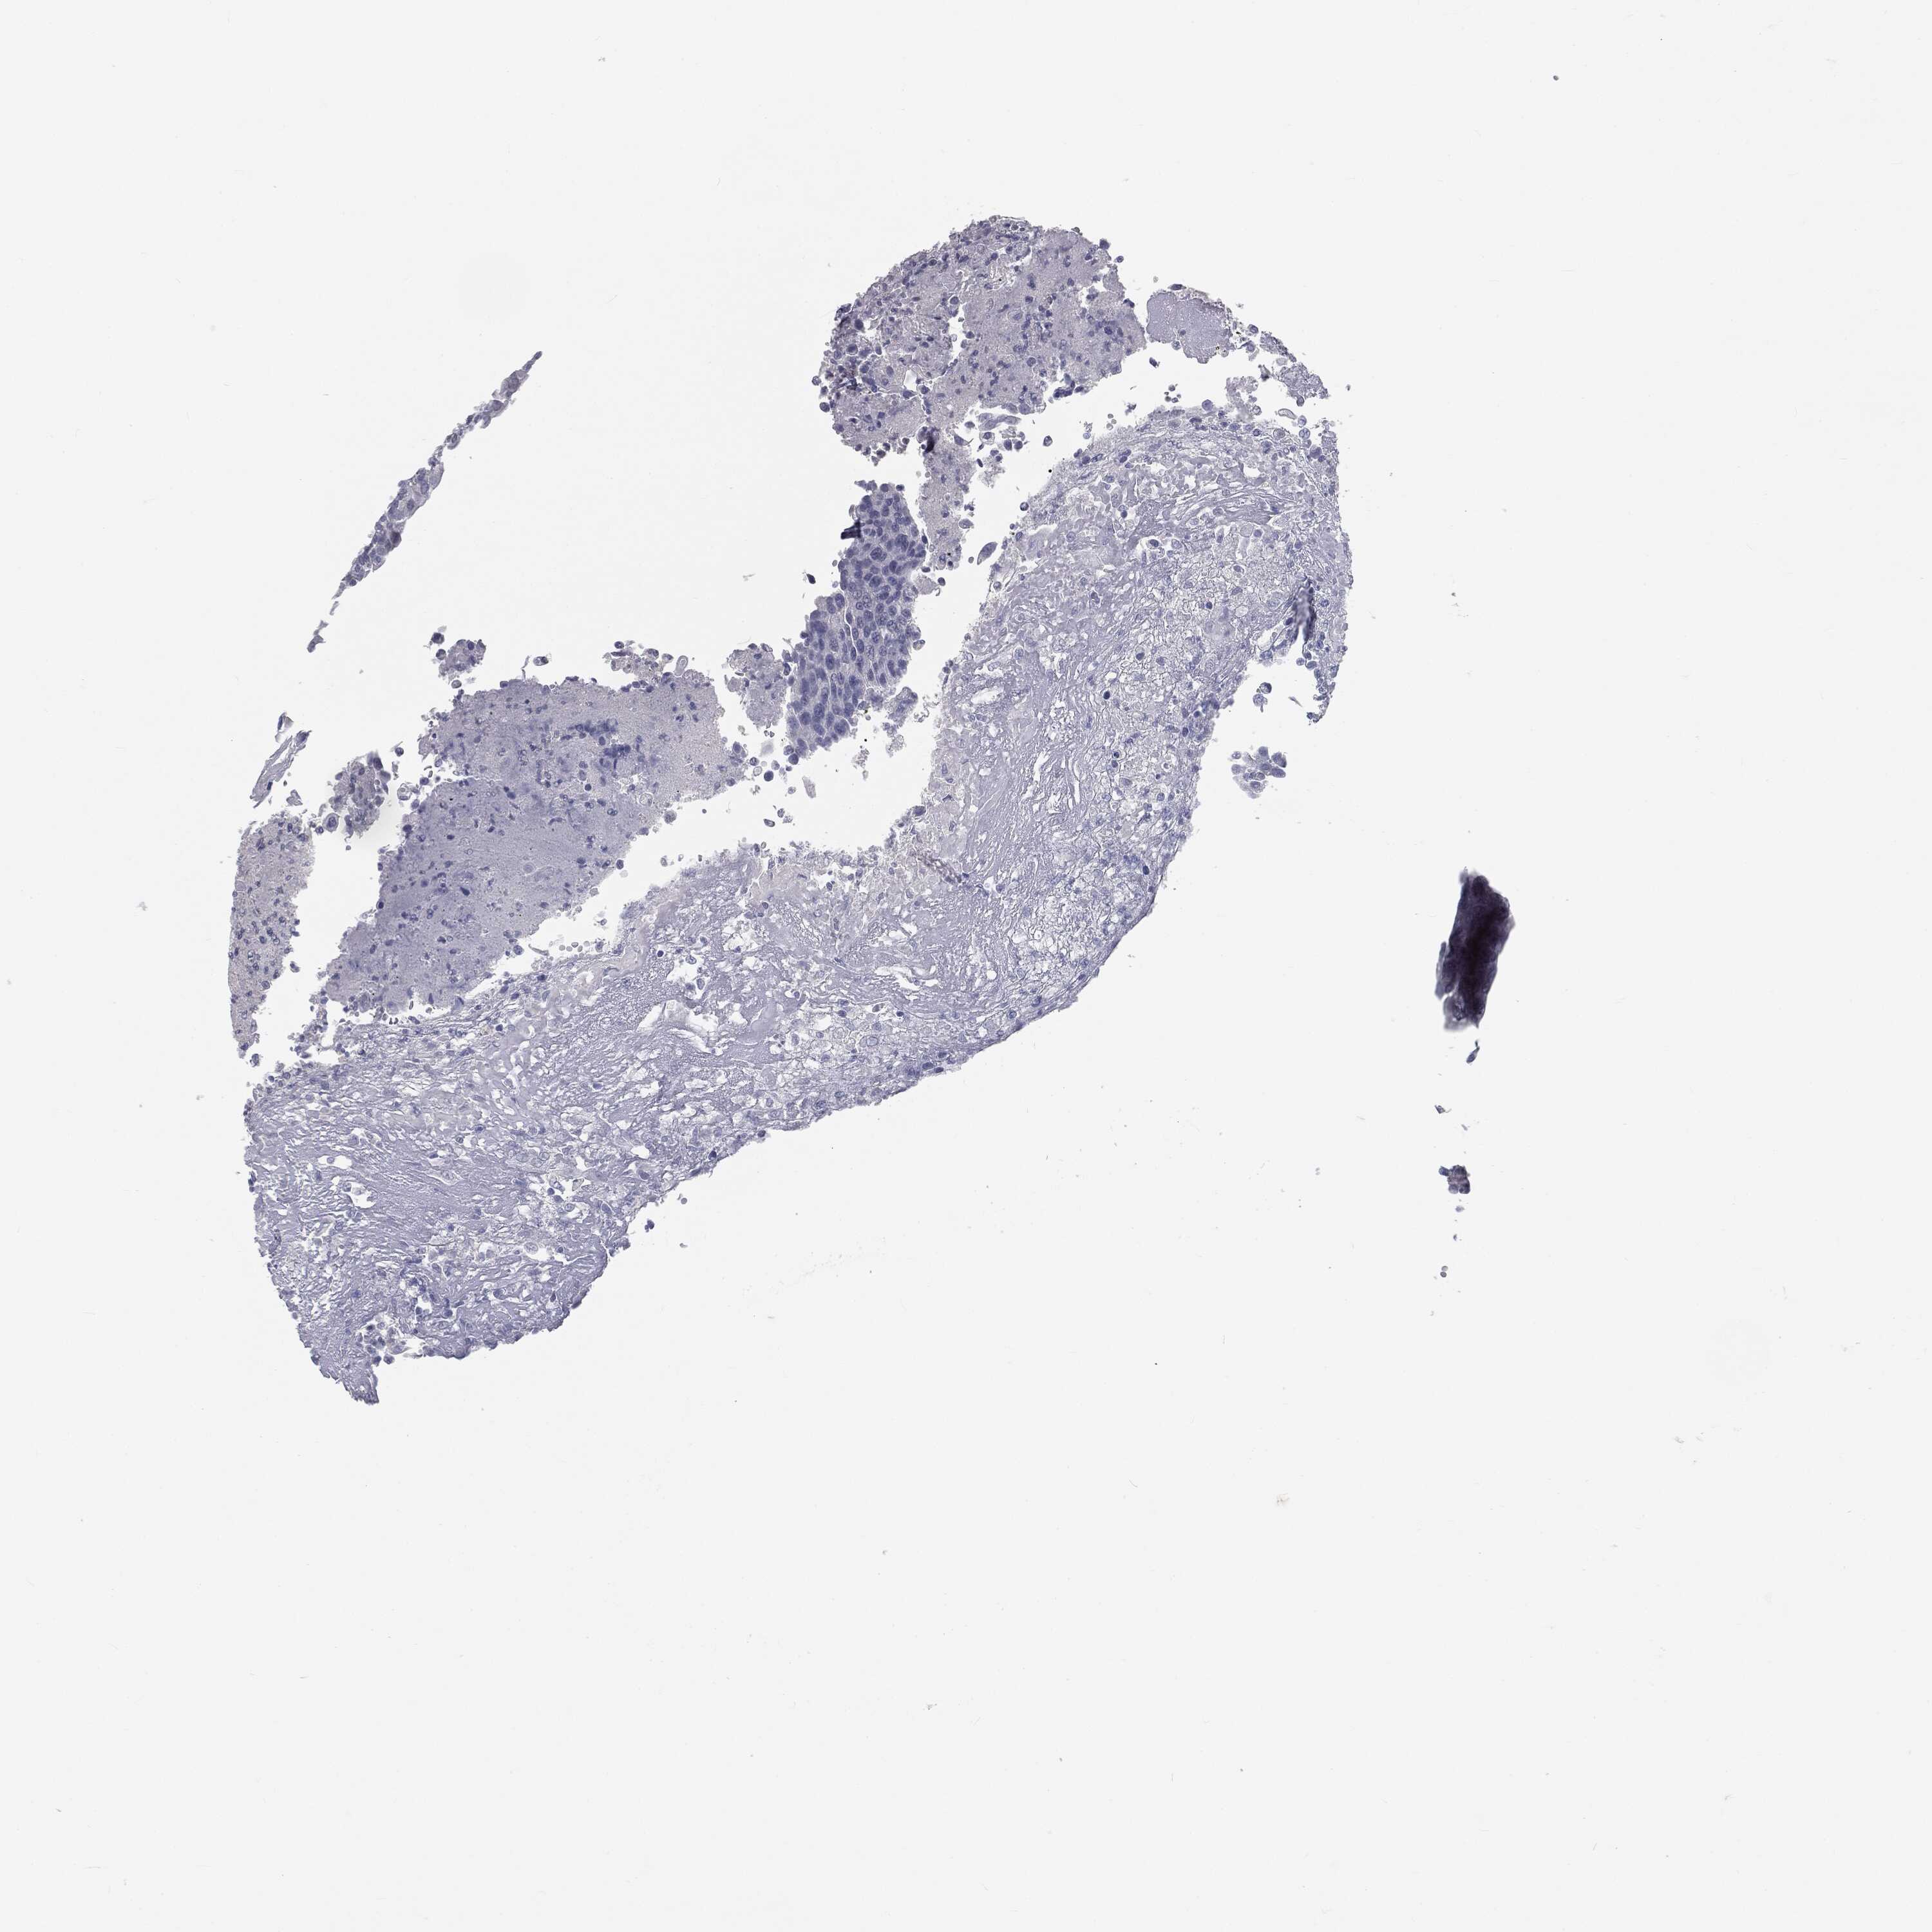

UROTHELIAL CANCER - Protein expressioni

A mouse-over function shows sample information and annotation data. Click on an image to view it in a full screen mode. Samples can be filtered based on level of antibody staining by selecting one or several of the following categories: high, medium, low and not detected. The assay and annotation is described here.

Antibody stainingi

Antibody staining in the annotated cell types in the current human tissue is reported as not detected, low, medium, or high, based on conventional immunohistochemistry profiling in selected tissues. This score is based on the combination of the staining intensity and fraction of stained cells.

Each image is clickable and will lead to virtual microscopy that enables deeper exploration of all samples and also displays staining intensity scores, fraction scores and subcellular localization as well as patient and tissue information for each sample.

Antibody HPA045153

Antibody CAB080138

Urothelial carcinoma, High grade

Urothelial carcinoma, NOS

Urothelial carcinoma, Low grade